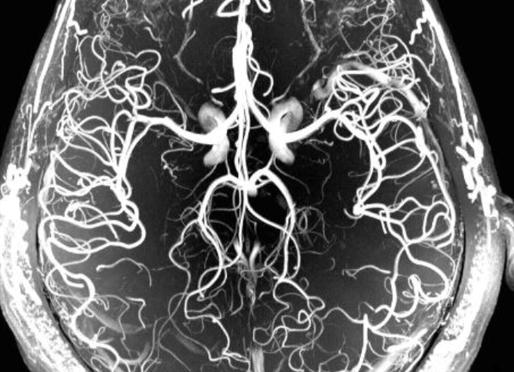

МР-ангиография сосудов головного мозга

МР-ангиография – эффективный способ исследования сосудов

МРТ артерий головного мозга методом ангиографии позволяет получать визуальные данные о состоянии сосудов без применения контрастных веществ. В некоторых тяжелых случаях с сомнительным диагнозом для четкой визуализации вен и артерий используют специальные контрастные средства с намагничивающимся компонентом.

Диагностический метод основывается на том, что выдаваемые томографом сигналы от крови в сосуде и окружающих его неподвижных тканях – различаются. Благодаря магнитно-резонансной ангиографии врач получает трехмерное изображение кровеносных сосудов в проекциях: фронтальной, аксиальной, саггитальной.

Для диагностики аневризм головного мозга в остром периоде субарахноидального кровоизлияния предпочтительна МР-ангиография, которая благодаря своей неинвазивности, высокой разрешающей способности, трехмерной проекции дает качественную картину сосудов головного мозга и позволяет определить источник проблемы.